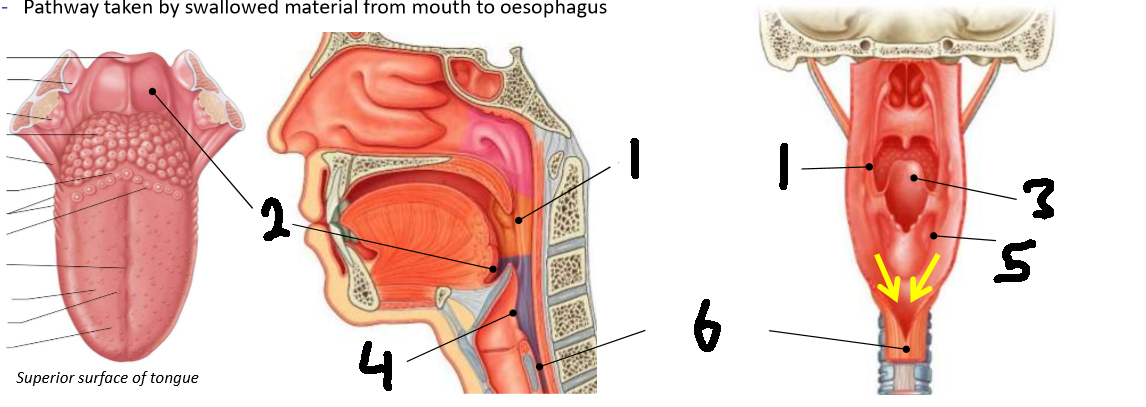

What is 1?

palatopharyngeal arch

What is 2?

vallecula

What is 3?

epiglottis

What is 4?

laryngeal inlet

What is 5?

piriform fossa

What is 6?

oesophagus